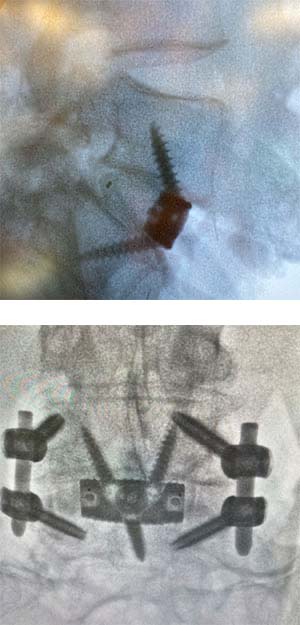

Spinal Fusion

Spinal fusion is a surgery that permanently connects two or more vertebra together, using one of several possible techniques. Under specific circumstances such as increased motion or advanced arthritis, a surgeon may elect to fuse vertebral bones together thus limiting motion which, result in decrease in pain.

Every prospective patient has heard of bad outcomes when it comes to spinal fusion surgeries. There are many cases where spinal fusion may be appropriate including increased motion or advanced arthritis.  After discussing with the patient and gaining an understanding of where the pain is coming from, a spine fusion may be the best care option and can be done minimally invasively with great outcomes. Fusion surgeries can be done minimally invasively and with great outcomes.

My goal is to provide care plans to patients once I fully understand where their pain is originating and can confidently say surgery will improve symptoms between 75-90%. Often, these techniques involve minimal muscle disruption and “indirect” decompression of nerves. These techniques involve less removal of bone and ligament and provide improved spinal alignment. A spinal fusion does create additional strain on adjacent spinal levels but when done correctly that adjacent strain can be mitigated. When these techniques are utilized, patients can spend much less time in the hospital and possibly even have the procedure performed in the outpatient setting, thus reducing costs. I follow all my patient post-operative outcomes and am always raising the bar to improve surgical results.